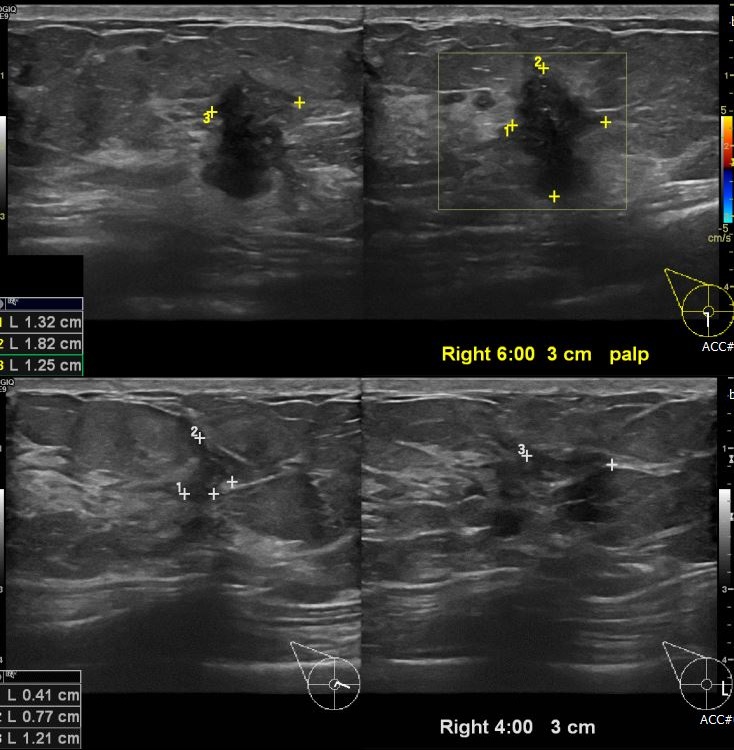

상기환자 우측 만져지는 멍울로 내원하신 40대 여성분으로 우측 6시 3cm 떨어진

거리의 의심스런 혹과, 4시 방향에서 3cm 떨어진 거리의 혹 각각 조직검사 시행하여

각각 우측 침윤성 유관암 진단 되었습니다.